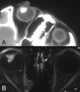

Medulloepithelioma

Medulloepithelioma is a rare, primitive, fast-growing brain tumour thought to stem from cells of the embryonic medullary cavity. Tumours originating in the ciliary body of the eye are referred to as embryonal medulloepitheliomas, or diktyomas.A highly malignant undifferentiated primitive neuroepithelial tumour of children, medulloepithelioma may contain bone, cartilage, skeletal muscle, and tends to metastasize extracranially. [Source: Wikipedia ]